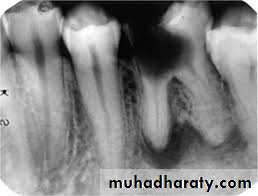

Sever and extensive periodontal disease is a common reason for tooth removal , in chronic periodontitis there is excessive bone loss and mobility in the tooth . As a rough guide loss of about half of the normal alveolar bone or extension of pockets to the bifurcation of the roots of posterior teeth and hypermobility of the teeth means that extraction of the involved tooth is necessary . Patient with advanced periodontitis may complains of mild to server throbbing pain in case of development of periodontal abscess .3- Pulp pathology :

4- Apical pathology :

Periapical lesions like periapical abscess , granuloma , cyst. If the teeth fail to respond to all conservative treatment to resolve apical pathology due to technical reasons or other causes such teeth are indicated for extraction .